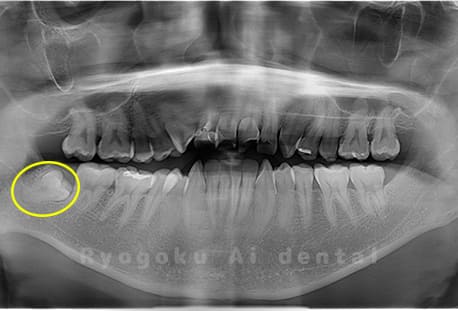

Case02

- 原因

- 下顎の水平埋伏智歯

- 治療内容

- 下顎の水平埋伏智歯を抜歯

<リスク・副作用>

手術後は痛み、腫れ、痺れなどの副作用が生じる場合があります。